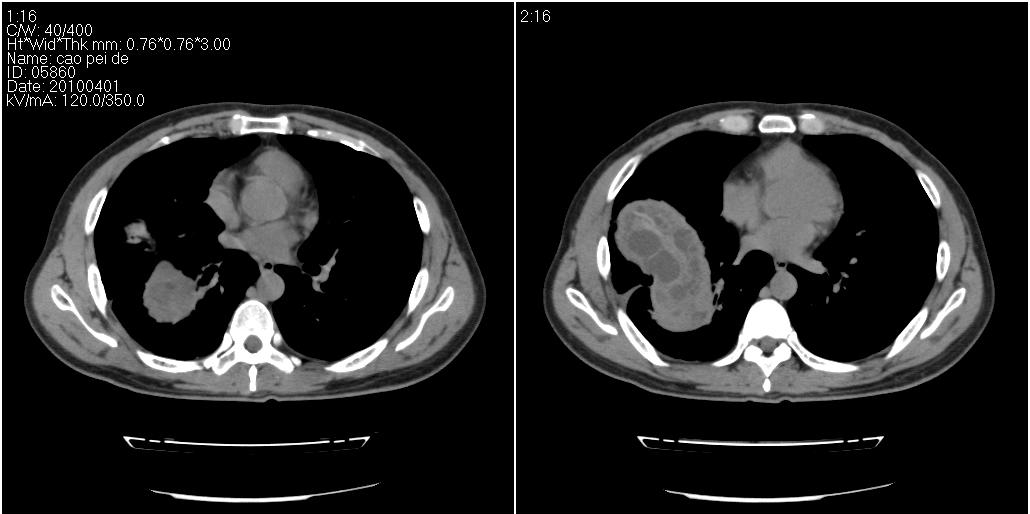

该患者70岁男性,手术后10年,现复查。2008年6月份本人曾经发过一极其类似的病例,只是部位略有差异。

多囊肝

肝脏多房性包虫囊肿

水上浮莲征,肝包虫囊肿。

肝脏及右侧胸腔包虫病。

大囊套小囊!肝脏多房性包虫囊肿